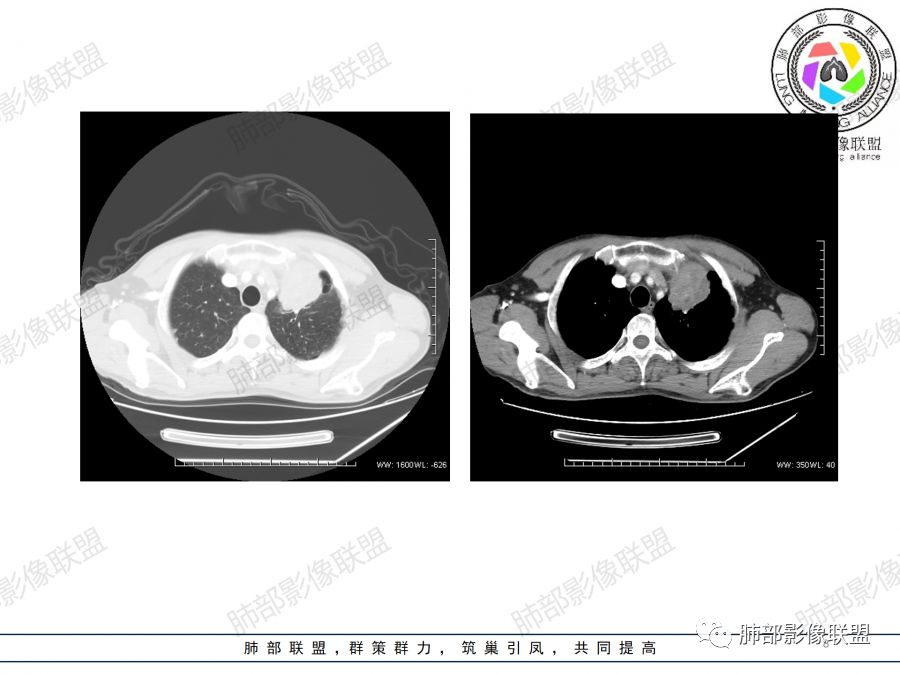

左上肺占位支气管阻塞伴肺不张、肿瘤不均匀强化,考虑鳞癌.

左肺上叶见实性结节,边缘可见分叶,周周可见磨玻璃影,病灶不均匀强化,中心可见坏死,部分坏死边界不清,部分呈环形,血管进入病灶内部,边缘逐渐变细截断,总体表现考虑恶性,腺癌。

中年男性,咳嗽咳痰一月。左肺上叶团块状软组织密度影,边缘部分清晰周围见磨玻璃影,增强后其内密度不均可见散在斑片状低密度区,血管造影征完整,团块邻近胸膜可见多发圆形低密度透光灶。左肺门处上叶血管似被包绕。左侧胸膜粘连肥厚。考虑1.左肺占位,淋巴瘤?鳞癌?2.因病灶内散在低密度待除外感染性病变可能

中年男性,咳嗽咳痰一月余入院胸CT:左肺上叶前段占位性病变,病灶内可见密度不均,可见低密度区,病灶可见分叶,增强病灶内可见血管征,血管边缘模糊,病灶近胸膜下呈膨胀性生长。诊断考虑:恶性病变。

40岁以上男性,中等病程,咳嗽,咳痰,左上块影,孤立,膨胀,胸膜受累,内密度高低不一,血管穿入,考虑肺癌,鳞?气管镜or穿刺!

左肺上叶肿块,强化不均匀,内见坏死,血管纤细,病灶周围有阻塞性炎,所见图像未见肿大淋巴结。考虑鳞癌可能大。

中年男性,亚急性起病,咳嗽,咳痰,左肺上叶肿块,边界清,膨隆,可见分叶,增强可见内部坏死,不均匀强化,部分边界累及胸膜,考虑恶性。

左肺上叶肿块,周周可见磨玻璃影,不均匀强化,内部可见坏死,部分坏死边界不清,血管进入病灶内,恶性肿瘤,考虑鳞癌。

分叶,破坏力不强,纵隔胸膜受累,周围阻塞性炎症,胸膜多发结节。考虑恶性,支持腺癌可能大。

左肺上叶肿块,边缘大部分平直,部分膨隆,周周可见磨玻璃影,不均匀强化,内部可见坏死,部分坏死边界不清,考虑恶性肿瘤,鳞癌可能大,病灶边缘大部分平直,不除外炎性。

患者中年男性,咳嗽、咳痰1月余入院。胸部CT:左肺上叶尖段近胸膜下肿块占位灶,边缘光滑,边界清楚,周围可见片状磨玻璃影,可见平直、毛刺、分叶征象,增强轻度强化,内可见点片多发低密度区及部分血管影,与支气管关系欠清,左肺上叶背侧胸膜增厚、胸膜下结节,右肺似见多发小结节灶,淋巴结不大。综合考虑良性病变,结核可能性大,鉴别腺癌并肺内、胸膜转移及淋巴瘤等。

左肺上叶见不规则肿块影,可见分叶,边缘膨隆部分边缘平直,增强后病灶可见不均匀明显强化,内见血管影,其血管边缘不光滑,周围肺野可见小结节病灶,考虑恶性病变,肿块与支气管关系显示不清,需要薄层,从肿块边缘平直来看应该有阻塞性肺炎和肺不张,偏向鳞癌。

胸CT:左上叶前段团块影,边缘部分清晰,近纵隔侧膨隆明显,分叶,肺侧见平直征,U形凹陷,病灶周围可见磨玻璃影,气肿带,纵隔多发淋巴结肿大,叶间裂多发小结节。增强病灶内密度不均,散在斑片状低密度区,血管造影征。考虑:恶性,鳞?腺?大细胞?鉴别:炎症。似有左侧胸廓内A供血病灶,SFT?

男,47岁,咳嗽咳痰一月余入院肺气肿背景。左上肺纵隔旁非均质肿块,分叶、膨隆,部分边缘光滑,肺门可见冰冻征,增强不均匀强化,见沼泽地样坏死,邻近肺组织见斑片状炎症,考虑恶性肿瘤,首先考虑小细胞癌,鉴别鳞癌。

47岁男性,咳嗽咳痰1月余。左肺上叶结节灶,形态不规则,边缘见分叶,其内可见斑片状低密度区。增强扫描呈轻度强化,侵犯纵隔及部分胸膜,综合考虑恶性!

中年男性,左肺上叶肿块、片状状影,形态不规则,边缘见分叶及磨玻璃影,其内可见斑片状低密度区及血管穿行。增强扫描呈轻度强化,侵犯纵隔及部分胸膜,纵隔见多发淋巴结肿大,定位:肺内,左上肺部分有不张;定性:偏恶性,侵犯支气管(病灶内见条状低密度影)但血管无明显受累,考虑粘膜相关性淋巴瘤(粘膜下起源)可能,结核待排;腺癌、鳞癌(血管无受侵不首先考虑),小细胞(无典型表现、虽然血管保留可见于小细胞);

首先定位肺内,理由是内乳动脉未见移位。左肺上叶前段肿块,边界清楚,边缘呈分叶状,增强扫描呈不均匀强化,内见边界不清无强化坏死区。同时于病灶内见多发迂曲走形边缘毛糙血管影。考虑恶性,建议穿刺。

左肺上叶不规则软组织肿块,分叶,病灶内密度不均匀,周围可见磨玻璃影,外侧可见局限性肺气肿,增强后轻度强化,病灶内强化血管增粗且模糊,坏死区无强化,纵隔淋巴结肿大,考虑恶性占位,鳞癌。鉴别结核。

男,47岁,咳嗽咳痰一月。病灶位于左内乳动脉内缘,定位肺内,呈团片状异常密度影,整体沿支气管气管束走形分布,由肺门达胸膜下,于近肺门侧病灶形态相对较小,病灶远端相对较大,病灶整体密度偏均匀,强化偏明显,病灶内见多发支气管扩张并粘液栓形成,且扩张支气管粗细不均,直达病灶以远,病灶内血管走形正常、粗细均匀,病灶周围见边缘模糊磨玻璃及少许腺泡结节。左肺门及纵隔略大淋巴结,左侧胸膜局限性增厚。诊断:左肺上叶前段异常密度影,炎性肉芽肿性病变可能,结核不能除外,建议穿刺活检除外恶性肿瘤。